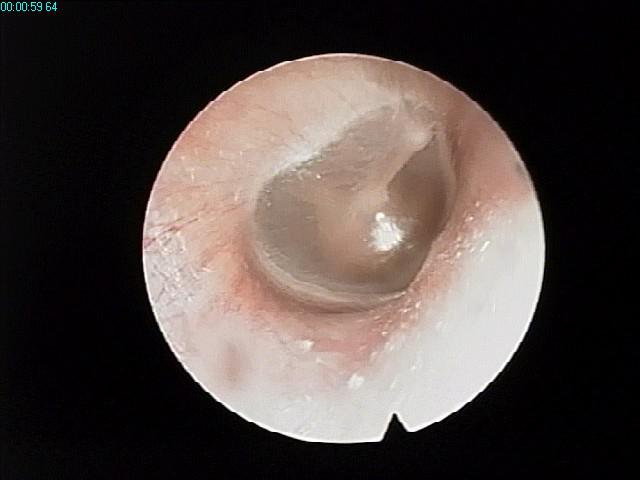

正常鼓膜 分泌性中耳炎鼓膜

2、功能障碍:司咽鼓管开闭的肌肉收缩无力;咽鼓管软 正常鼓膜 分泌性中耳炎鼓膜